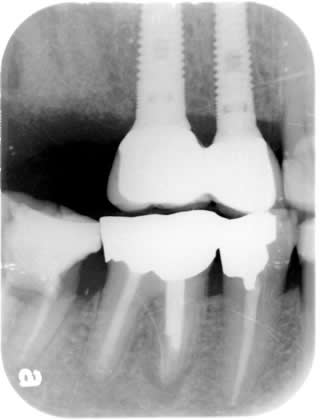

Implant Crowns:

April 2009

Splinted Crowns are cemented onto the two implants.

Imlants crowns are usually splinted together to enhance lateral oblique biting force.